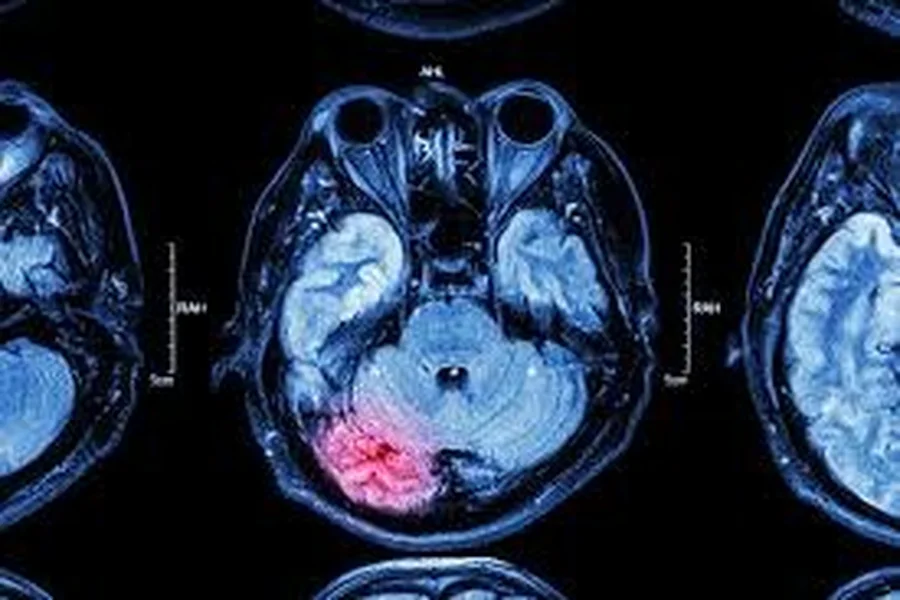

The Hidden Costs Of Tbi In South Carolina Personal Injury Cases

You face significant challenges if a loved one suffers a traumatic brain injury (TBI) in South Carolina. These injuries can […]